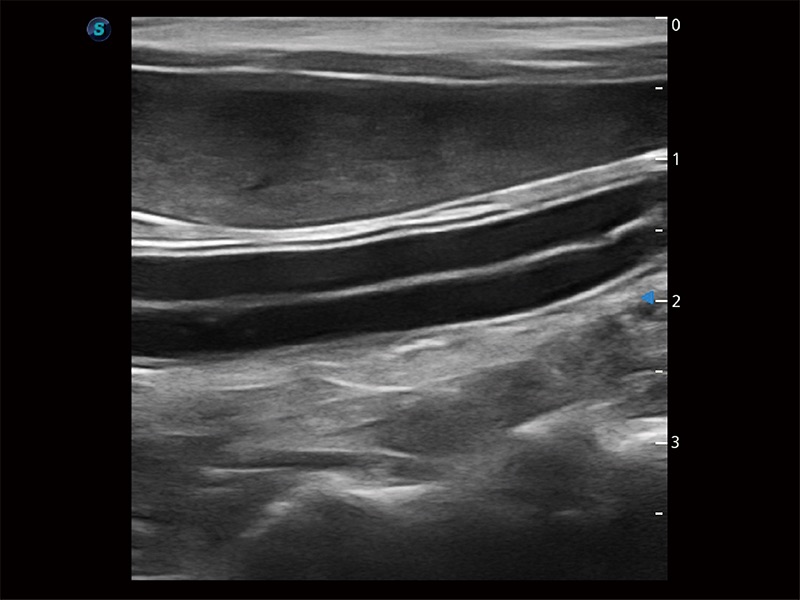

ProPet 80 全新的动物超声智能软件和丰富的探头群,为动物医生提供了高清晰度和精细分辨率的图像,无论在宠物、马科、畜牧还是实验室动物等应用中都可以轻松应对,为您的日常工作带来满意的体验。